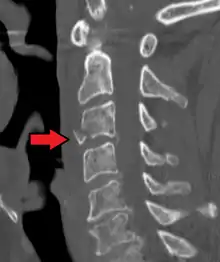

![]() | |

| A fracture of the base of the dens (a part of C2) as seen on CT. | |